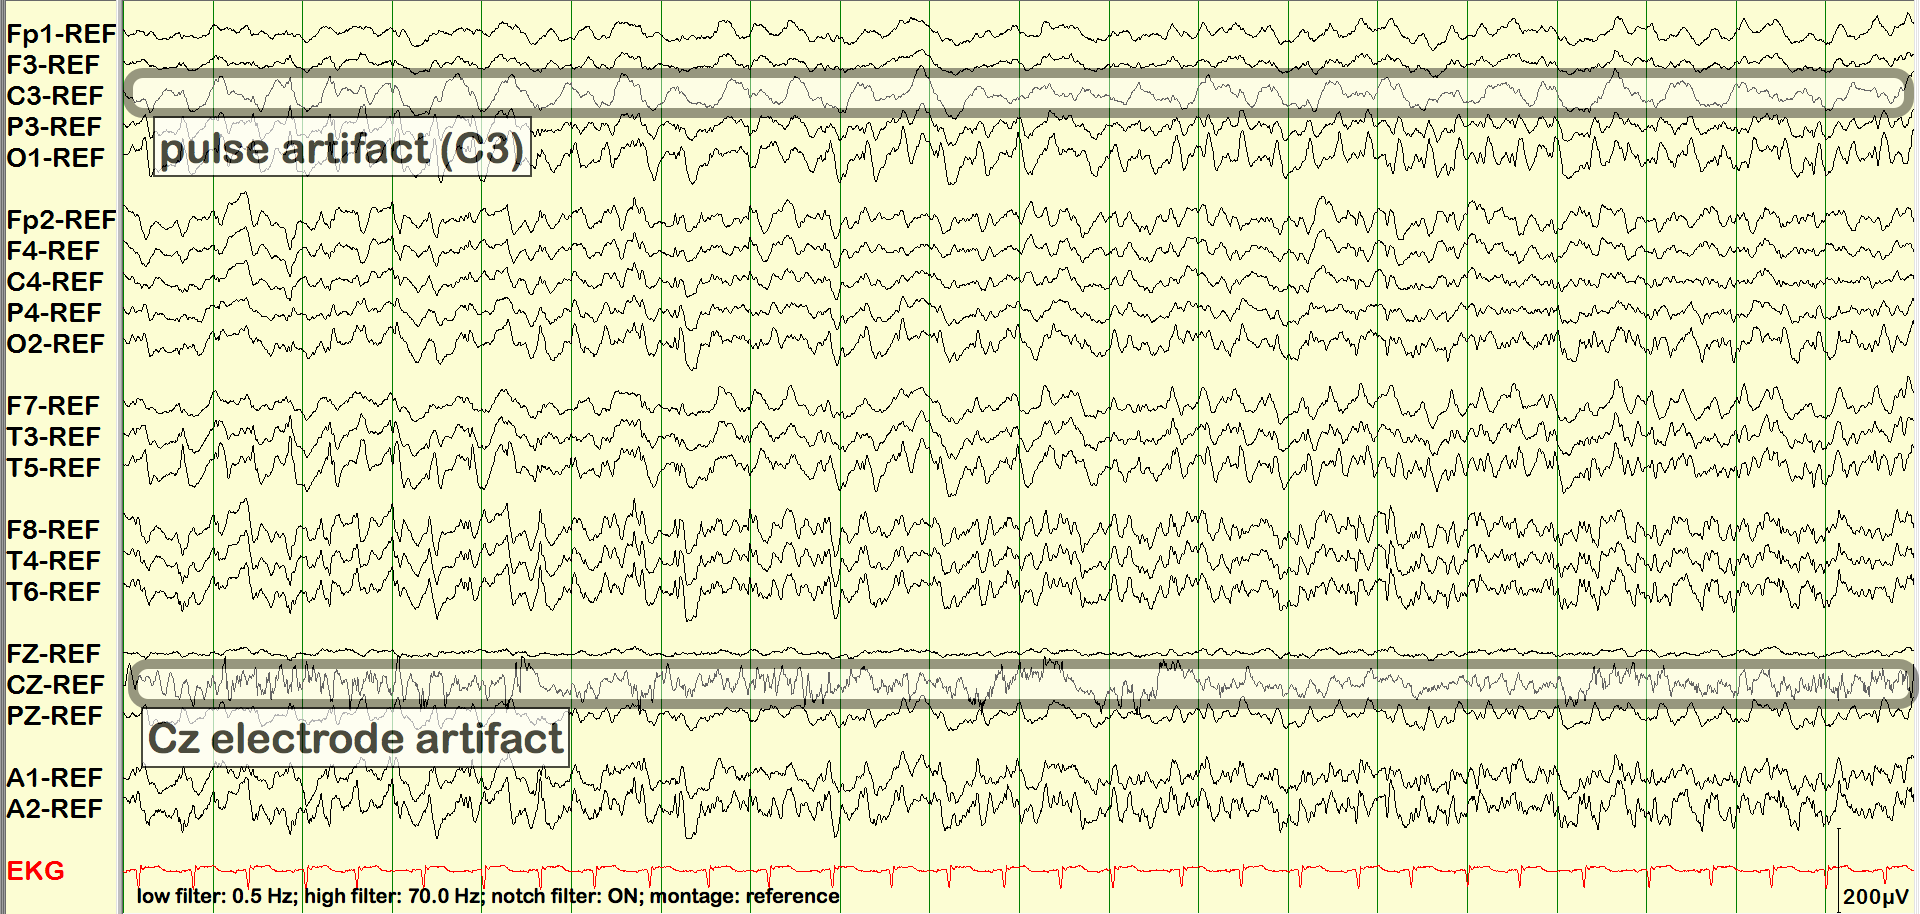

Pulse Artifact

In the following example, the pulse artifact in C3 is seen to stay synchronized with the EKG over the entire 3 minute and 15 second clip.